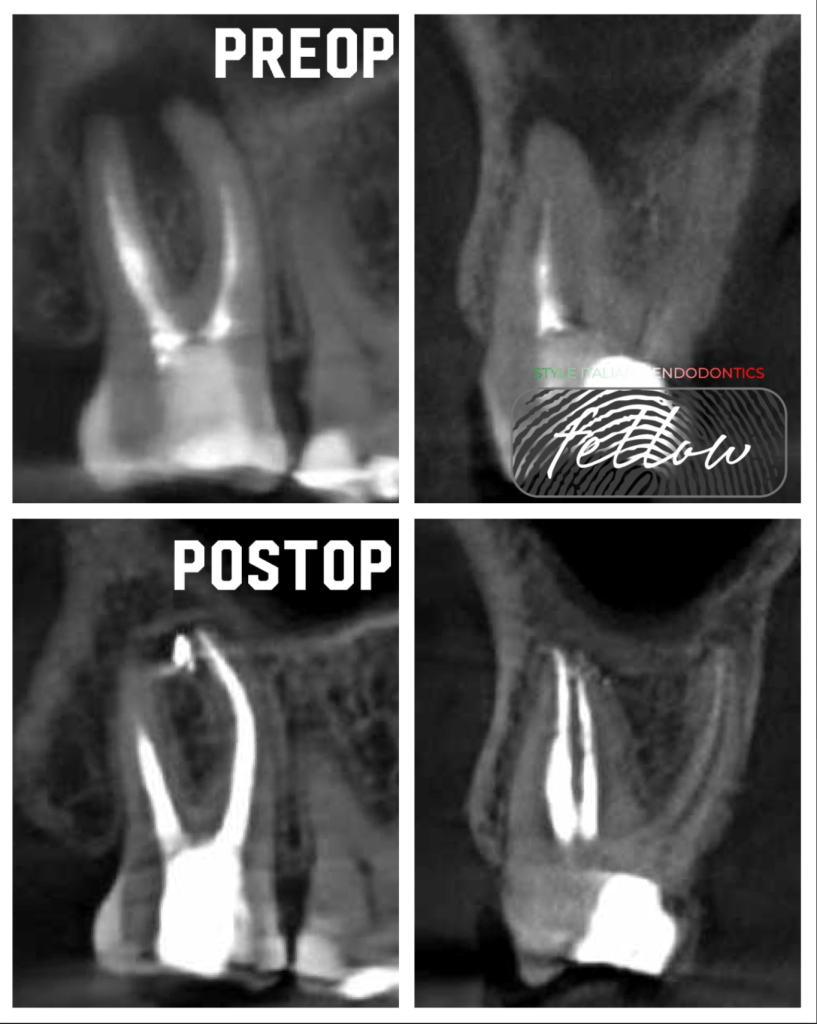

Premolar calcificado lesion